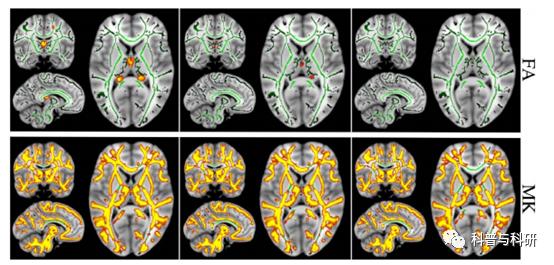

扩散成像处理实操 |

1、TBSS分析方法介绍 2、TBSS数据批处理实现 3、TBSS数据分析实操 4、结果呈现 |

扩散成像处理实操 |

1、DTI基本原理、常用分析方法和预处理 2、TBSS数据批处理实现 3、TBSS数据分析实操以及结果呈现 4、其它DTI数据分析方法概述 |

(1)基于白质骨架的弥散统计分析(TBSS)

1头动涡流校正(eddy_correct):在一定程度上消除扫描过程中的头动,以及由头动和涡流所引起的形变等

2梯度方向矫正(fdt_rotate_bvecs):将原来的梯度方向根据涡流矫正的变化进行调整

3获取大脑mask(fslroi):计算张量前,需要先得一个mask图像来确定张量计算范围,一般通过b0图像得到对应的mask。

4张量计算(dtifit):利用FSL中的dtifit功能(命令或界面)计算张量,同时获得FA、MD、AD、RD值等相关标量指标